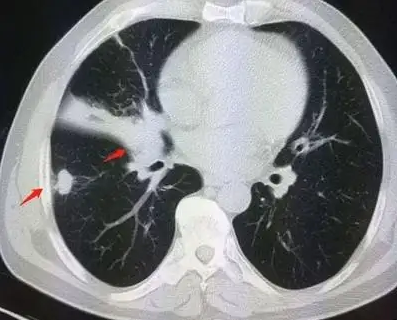

肺部有结节是怎么回事?要紧吗?肺结节是直径小于或等于3cm的局灶性、类圆形、密度增高、实质性或亚实质性肺部阴影。当肺部小结节出现时,很难判断它们是良性还是恶性,但绝大多数结节都是良性的。

1.纯磨玻璃结节:它们看起来像薄雾,可分为两类。弥漫性生长通常是良性的,而局灶性生长通常是恶性的。

2.混合磨玻璃结节:四周脱盐,中间实心。看起来像个荷包蛋。这种恶化是最严重的。实性成分越多,就越可能是恶性的。

3.实性结节:只有一个实体。这种结节通常钙化,良性的可能性高。